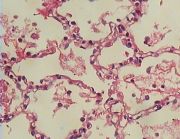

| 2021年12月10日 (五) 13:22 | 23 号切片-大叶性肺炎-镜下观4-崩解期-中性粒细胞变性崩解, 纤维素被溶解,肺泡内重新含气。.jpg (文件) |  |

145 KB | Cirno.9 | 基于MsUpload的文件上传 | 1 |